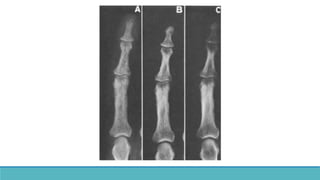

• Cortical bone erosion – Phalanges

•Most sensitive site : Radial aspects of

middle phalanges of index and middle

fingers.

• Tufts of distal phalanges.

• Cortical boneerosion – Phalanges •Most sensitive site : Radial aspects of middle phalanges of index and middle fingers. • Tufts of distal phalanges. •Acrosteolysis – distal phalanges, Outer clavicle, pubic symphysis, sacroiliac joints, proximal medial cortex of tibia, proximal humeral shaft, ribs and femur.